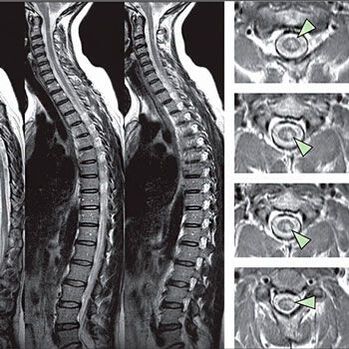

Za účelem identifikace příznaků poruch citlivosti se provádějí speciální funkční testy. Nejoblíbenější možností diagnózy z instrumentálních metod je výkon x -ray. Pro důkladnou studii páteře se však často provádějí MRI a CT. V případě podezření z onemocnění kardiovaskulárního systému se pacient doporučuje podstoupit postup ECG.